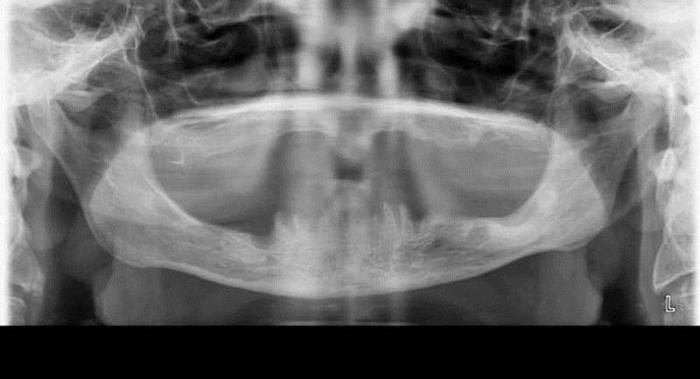

Адентия — это отсутствие зубов. Если в челюсти не хватает нескольких зубов, это называется частичной адентией, а если отсутствуют все — полной. Стоматолог проведет диагностику для выявления причины адентии. Рентгенограмма покажет наличие зачатков молочных зубов в челюсти ребенка и поможет выяснить, почему они не прорезываются.

Для диагностики адентии у детей используются клинические и инструментальные методы. Первоначально врач проводит визуальный осмотр полости рта, обращая внимание на количество зубов, их состояние и развитие челюстей. При выявлении отсутствия зубов рекомендуется применять рентгенографию. Этот метод позволяет оценить наличие зачатков зубов, что важно для определения причин адентии.

Второй этап диагностики включает использование панорамной рентгенографии, которая дает возможность получить полное изображение всех зубных рядов и челюстей. Это помогает выявить не только адентию, но и возможные патологии, такие как аномалии развития зубов или челюстей.